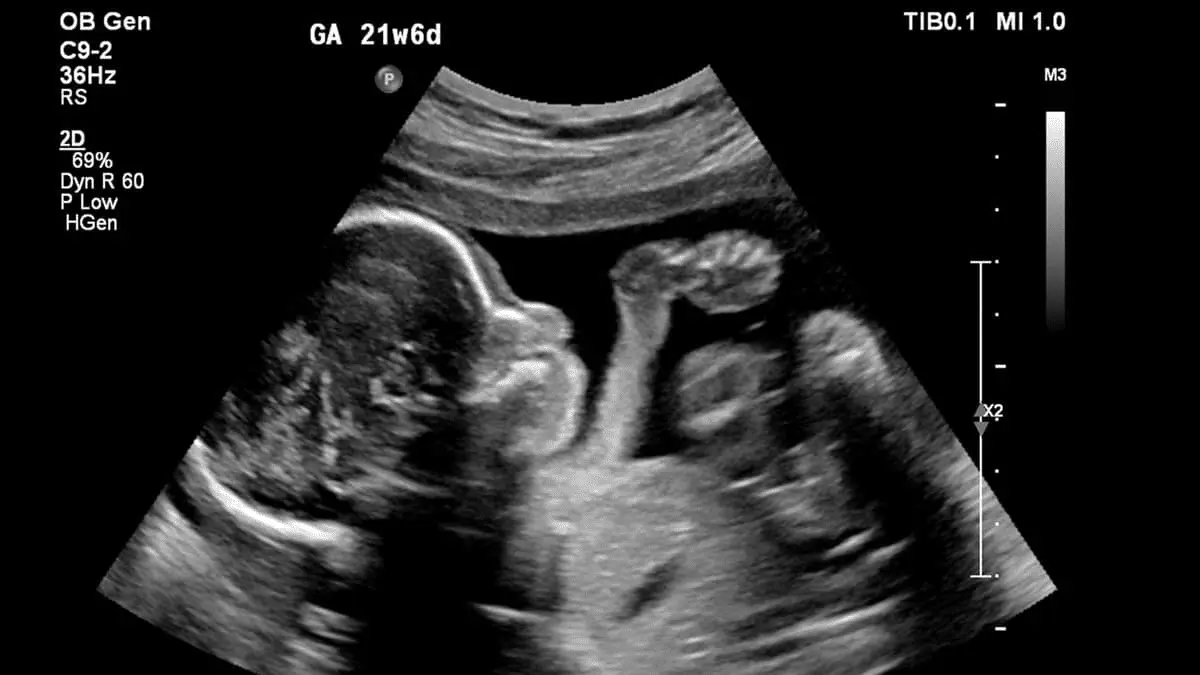

I understand, you want to kill without restraint and without remorse for your acts. So you seek to dehumanize your victims. A hundred years ago, Sanger and her creepy fellow travelers like Adolf Hitler got away with it to some degree. But now we have this,

View attachment 727998

We know what's inside - you ghouls can no longer lie - all you can do is deny science.

Thanks for that ultrasound image

If that is not a child....